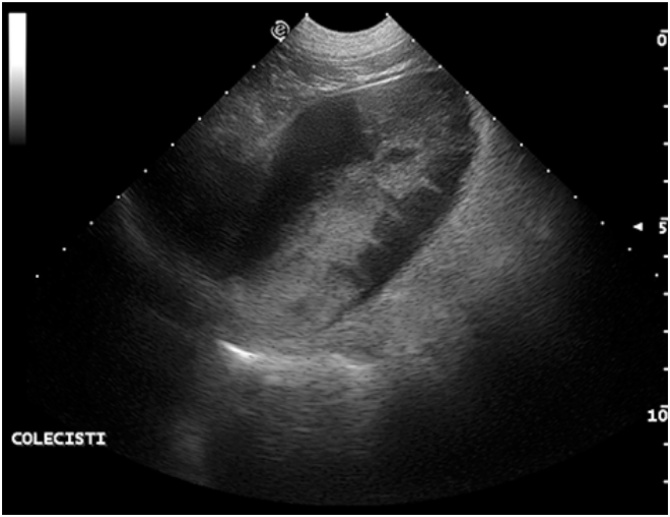

Liver Ultrasonography is indicated primarly in cases of chronic diseases (hepatic insufficiency, fat parenchyma infiltration, focal parenchymal lesions) and in their follow up. Characterization of liver primary/metastatic expansive masses should be considered. The presence of hepatic fluid filled cysts in cats may be associated to a congenital disease called Policystic Kidney Disease (PKD) frequently observed in exotic and Persian cat [29]. The characterization of the malignancy of multiple parenchymal liver nodules can be studied by means of ultrasonographic contrast medium [30,31]; the evaluation of the portal venous phase is able to discriminate among benign and malignant nodules with a high sensitivity and specificity as it is described in human medicine [32]. Ultrasonographic evaluation of the gallbladder and common bile duct may outline thickening of the wall suggestive of colecistytis; its contents with the common “kiwi pattern appearance” may suggest the presence of mucocele (Fig. 13) [33]. Gallbladder calculi, expansive masses, common bile duct obstruction are other conditions that can be described ultrasonographically. Doppler evaluation of the portal vein flow, when indicated, may outline conditions of portal hypertension, or conditions of portal-cava shunts.

Fig. 13.

Mucocele in a 12-years old female Mixed breed dog: sagittal oblique scan of the gallbladder. Within the anaechoic lumen of the gallbladder, echoic structures suggestive of a “kiwi pattern” are visible.